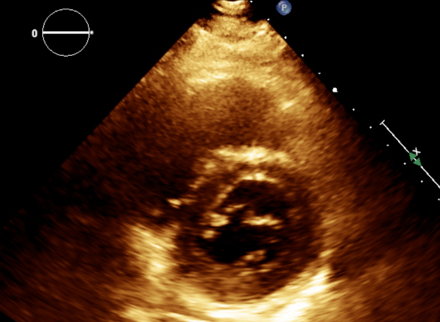

A middle-aged man with a history of asthma and chronic sinusitis presented with pleuritic chest pain, breathlessness, and numbness in his left arm. On examination, he was hypertensive, tachypneic, and hypoxic. Laboratory workup showed leukocytosis with marked eosinophilia (13.09 x 10^3/μL), elevated cardiac biomarkers, and proteinuria. Computed tomography angiography revealed subsegmental pulmonary embolism. Echocardiography showed a moderately dilated right ventricle with reduced systolic function. Cardiac imaging identified diffuse myocardial edema, subendocardial enhancement in the right ventricle, and an apical thrombus. Cerebral magnetic resonance imaging revealed multifocal diffusion-restricted lesions. Coronary angiography showed no obstructive disease. Given the constellation of asthma, eosinophilia, neuropathy, and sinus disease, eosinophilic granulomatosis with polyangiitis (EGPA) was strongly considered. Testing for clonal eosinophilic syndromes and antineutrophil cytoplasmic antibodies was negative. Immunosuppressive therapy, including Rituximab and Mepolizumab, was initiated. Follow-up imaging at 9 months demonstrated complete resolution of myocardial inflammation and thrombus.

Cardiac involvement in eosinophilic granulomatosis with polyangiitis is a major determinant of morbidity and mortality, contributing to nearly half of EGPA-related deaths. Clinical manifestations may include myocarditis, pericarditis, heart failure, or intracardiac thrombus. However, cardiac EGPA often lacks classic ischemic findings, making diagnosis challenging. Cardiac magnetic resonance imaging is the most sensitive modality for detecting myocardial inflammation, subendocardial fibrosis, and mural thrombus, particularly when endomyocardial biopsy is contraindicated. In this case, cardiac magnetic resonance imaging provided critical diagnostic clarity, revealing diffuse myocardial edema and subendocardial enhancement, features consistent with eosinophilic myocarditis. Integration of imaging findings with peripheral eosinophilia, asthma, neuropathy, and sinus disease enabled the timely recognition of EGPA. This case underscores the importance of early, multimodal cardiac imaging in patients with unexplained cardiac dysfunction and eosinophilia to prevent irreversible damage through targeted immunosuppression.